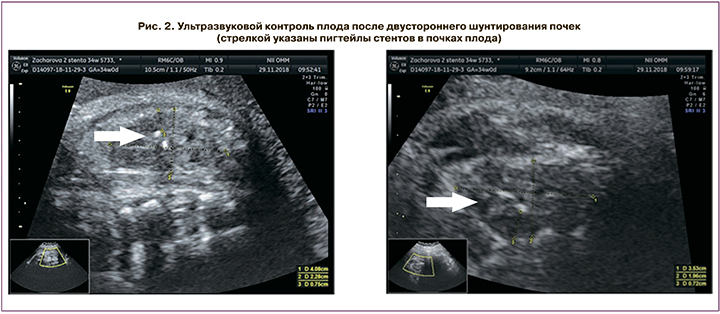

Пациентка К., 27 лет, поступила в плановом порядке в ФГБУ «НИИ ОММ» МЗ РФ с диагнозом: Беременность 30–31 неделя, врожденный порок развития мочевыделительной системы у плода: признаки двустороннего гидронефроза. Прегравидарная подготовка проводилась. На диспансерном учете с 9 недель. Течение I триместра без особенностей, первый ультразвуковой скрининг – без особенностей. По данным УЗИ II триместра беременности выявлены признаки двустороннего гидронефроза. В сроке 28 недель пациентка была направлена на консультативный прием в ФГБУ «НИИ ОММ» МЗ РФ для уточнения внутриутробного состояния плода с дальнейшим решением вопроса о необходимости применения внутриутробной коррекции порока. По данным УЗИ плода выявлено: левая почка 41×51 мм, паренхима до 2 мм, кровоток не визуализируется, чашечно-лоханочная система расширена, лоханка 58×45×49 мм, чашечки до 10 мм, IV стадия гидронефроза. Правая почка 55×37 мм, паренхима 4 мм, кровоток визуализируется, чашечно-лоханочная система расширена, лоханка 37×26 мм, чашечки до 5 мм. Поставлен диагноз: двусторонний гидронефроз, слева IV, справа II–III степени. После коллегиального обсуждения было решено провести нефроамниальное шунтирование правой почки в 30 недель беременности. Через 14 дней после шунтирования и повторного коллегиального обсуждения было решено установить стент в левую почку в сроке 32 недели беременности (в правой почке стент визуализировался). После проведения шунтирования почек плода пациентка еженедельно наблюдалась. Экспульсии стентов не произошло (рис. 2).

Срочные роды через естественные родовые пути произошли в сроке 39–40 недель беременности, родился мальчик 3450 г, 54 см. Клинический диагноз ребенка при поступлении в отделение хирургии новорожденных ОДКБ №1 г. Екатеринбурга: Врожденный порок развития мочевыделительной системы: двусторонний гидронефроз III–IV степени. Вторичный хронический пиелонефрит. Нейрогенная дисфункция мочевого пузыря. Скрытый половой член. Крипторхизм слева, брюшная ретенция. Двустороннее внутриутробное шунтирование почек. Шунты у новорожденного функционировали с обеих сторон. На 7-е сутки жизни проведена люмботомия слева, широкий пиелоуретеральный анастомоз на стенте слева». Справа стент-эндопротез «СДЕ-МЕД» был оставлен и функционировал в течение 1,5 месяцев, после чего при повторной госпитализации был эвакуирован. Оперативной коррекции порока справа не потребовалось, в настоящее время справа сохраняется пиелоэктазия.